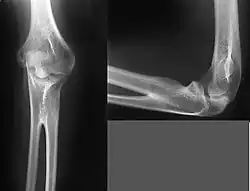

Ein Röntgenbild bestätigt die Diagnose aufgrund der typischen Fehlstellung des proximalen Radius, nicht abgrenzbarem Radiuskopf und Nachweis der Synostosierung.

Abzugrenzen ist die Ellbogenaplasie, eine Humeroradioulnare Synostose und die Kongenitale Radiuskopfluxation.